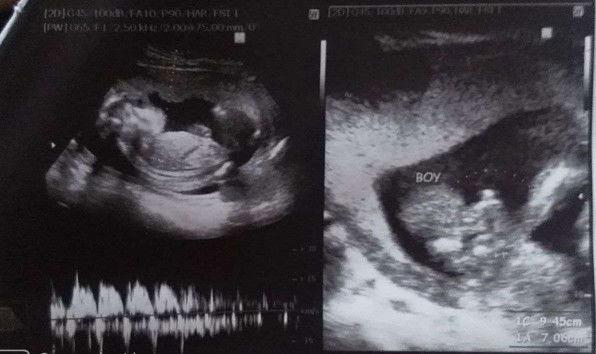

Boy ba?

Hello mga momshie patingin naman po kung boy po ba talaga baby ko,nkita nila kasj gender niya noong 18weeks ako ,and then lumipat ako ng OB dahil umuwe nako ,nakita ng Ob ung ultrasound ko sabi nya"Owss boy ba to ? Hindi naman ata e parang ung pusod" and after nung sinbi nya yan mga sis chineck nya si baby ko para tignan if boy nga ba kaso po ayaw magpakita gender n baby ko nung 24weeks ako na nagpacheck up.Naguguluhan kasi ako mga sis ,patulong ang mahal pa naman binayad ko sa first ultrasound ko🤦 28 weeks na ako bukas mga sis❤️